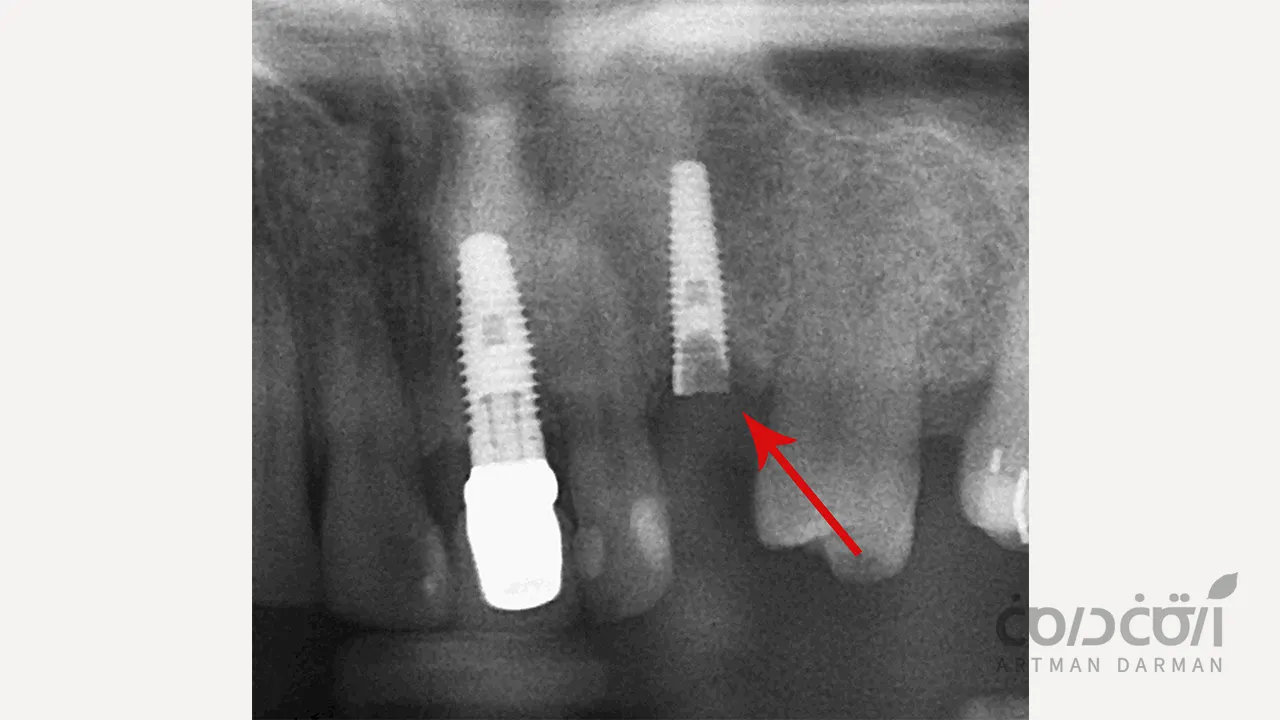

در یک شکستگی ایمپلنت دندان واقعی، خود پایه تیتانیومی که به طور کامل به استخوان جوش خورده است، دچار ترک یا شکست کامل می شود. این شکستگی معمولاً در ضعیف ترین نقطه ایمپلنت، یعنی در ناحیه گردن آن (نزدیک به محل اتصال به اباتمنت) رخ می دهد.

- تهیه رادیوگرافی (X-ray): این مهم ترین ابزار تشخیصی است. در رادیوگرافی، یک خط شکست واضح در بدنه ایمپلنت قابل مشاهده است. گاهی برای بررسی دقیق تر، از اسکن سه بعدی (CBCT) استفاده می شود.

این مرحله، چالش برانگیزترین بخش درمان است. قطعه بالایی ایمپلنت که شکسته و لق است، به راحتی خارج می شود. اما قطعه پایینی (آپیکال) هنوز به طور کامل به استخوان جوش خورده است (اوسئواینتگریشن). خارج کردن این قطعه بدون آسیب رساندن شدید به استخوان اطراف، نیازمند تکنیک و ابزارهای خاص است.